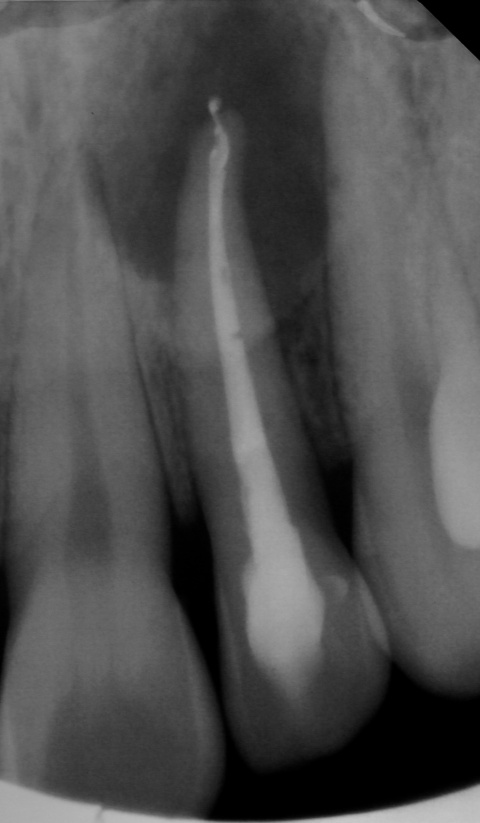

Zahn 21, Hinweise auf möglicherweise

überpresstes Wurzelfüllmaterial im apikalen Bereich.

Wurzelfüllung sowie Hinweise auf eine vorhandene

Via falsa.

Im Januar 2019 stellte sich ein 52-jähriger Soldat mit einem auf Gingivaniveau abgebrochenen Zahn 21 im Rahmen einer Notfallbehandlung bei uns vor. Zur Wiederherstellung der Ästhetik, Phonetik und Beißfunktion wurde die Krone in direktem Verfahren wieder aufgebaut. Das anschließend angefertigte Röntgenbild zeigte eine zu kurze und inhomogene Wurzelfüllung mit Hinweisen auf eine vorliegende Via falsa.

Gleichzeitig berichtete der Patient über Beschwerden am Zahn, welche wiederholt auftraten und sich durch Druck auf das Vestibulum reproduzieren ließen. Eine Schwellung, Fistelung oder erhöhte Sondierungswerte lagen zu diesem Zeitpunkt nicht vor. Da zur Aufnahme einer laborgefertigten Restauration eine vorherige Stiftinsertion geplant war, vereinbarten wir zunächst die Revision der vorhandenen insuffizienten Wurzelfüllung. Trotz Dentalmikroskop und vorgebogenen Ultraschallfeilen ließ sich der ursprüngliche Kanalverlauf während der Revisionsbehandlung nicht mehr darstellen (Abb. 3 zeigt den Verlauf der Via falsa).